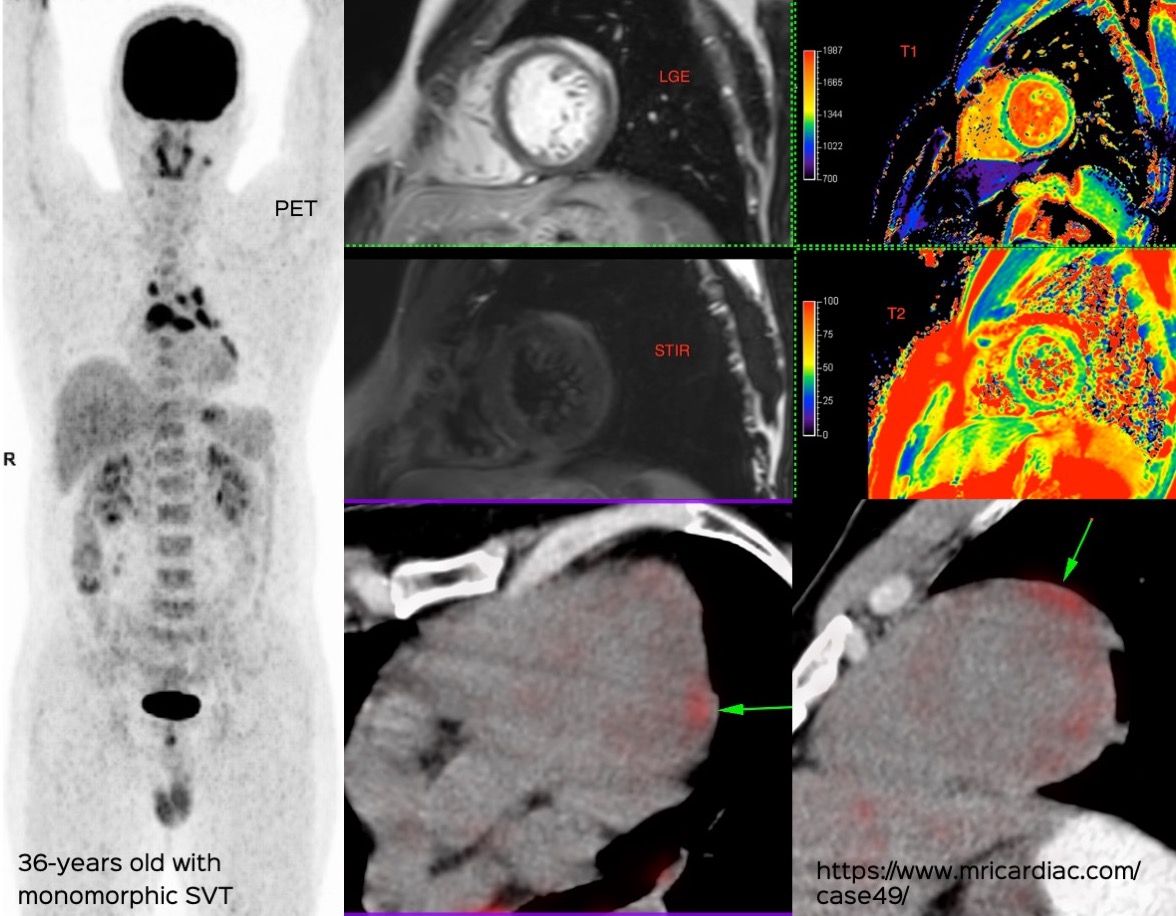

Cardiac MRI is a useful tool to diagnose amyloidosis. T1 mapping has become a mainstay, both native and ECV measurements. ECV measurement can now help quantify the amyloidosis burden and may help guide treatment based on how the ECV responds to specific treatment measures.